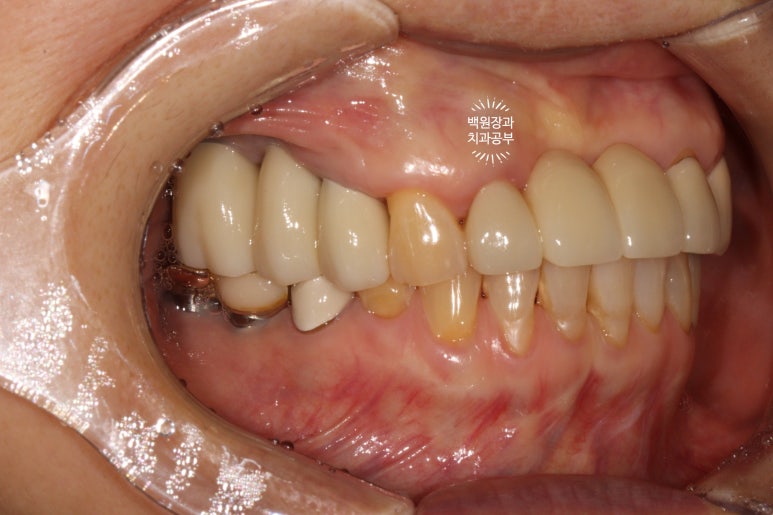

정면에서 보았을 때는 잘 보이시지 않을 수 있으나,

측면에서 보았을 때, 처음에 저희 병원에 내원하셨을 때에 비해 많이 길어지지 않고 비슷한 길이의 크라운으로 제작된 것을 확인하실 수 있을겁니다.

수술 전에 비해 약 1-2mm 정도 임플란트 크라운이 길어진 느낌이네요.

체감이 잘 안되실 수 있으나... 치과의사들이 보면 나름 흥미로움을 느낄 수 있는 결과라고 할 수 있죠!

좌측은 깔끔하게 마무리된 지르코니아 브릿지를 보실 수 있네요 :)